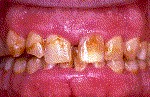

Periodontitis Leve.- Sangrado más pronunciado e hinchazón en las encías, las encías comienzan a despegarse de los dientes, mal aliento y gusto, bolsas de 3-4 mm de profundidad.

Periodontitis Moderada.- Los dientes se ven más largos debido a la retracción, pueden desarrollarse abscesos, mal aliento y mal gusto, los dientes pueden comenzar a moverse y a mostrar espacios, bolsas de 4-6 mm de profundidad.

Periodontitis Avanzada.- La movilidad dentaria puede incrementarse, Mal aliento y mal gusto constantes,  Sensibilidad dentaria debido a la exposición de las raíces, Bolsas mayores a 6 mm, Pueden perderse algunos dientes.